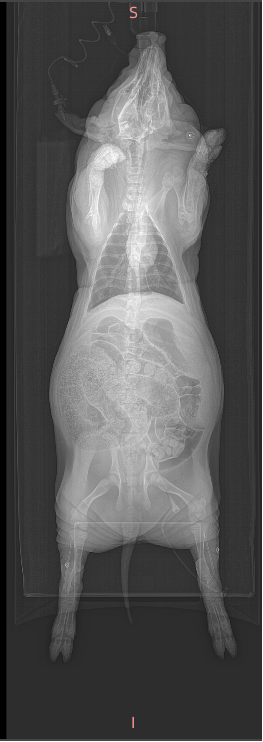

CT、Micro-CT

Micro-CT的应用

1、对离体动物的骨骼、牙齿、生物材料等样品进行二维/三维的成像;

2、可在造影剂的辅助下,对活体动物的血管、骨骼、脏器、泌尿等系统进行二维/三维的成像;